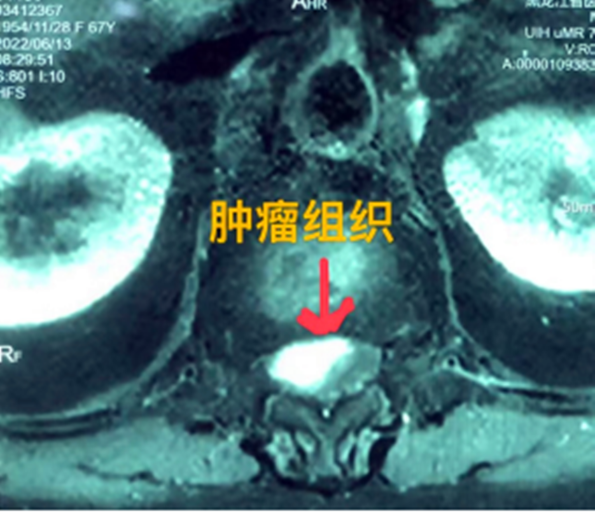

據(jù)省醫(yī)院神經(jīng)外一科陶宇醫(yī)生介紹,家住外地的張大娘最近總感覺(jué)雙下肢疼痛、無(wú)力,且排尿困難及便秘,伴有行走困難。時(shí)間長(zhǎng)了,張大娘病情逐漸加重,劇烈的疼痛甚至讓她無(wú)法完整入睡。在當(dāng)?shù)蒯t(yī)院,張大娘按腰椎肩盤突出接受治療,但未見好轉(zhuǎn),隨后進(jìn)行的胸椎MRI(核磁共振)檢查,結(jié)果不禁讓張大娘和家屬瞠目結(jié)舌,原來(lái)張大娘患的竟然是少見的脊髓腫瘤。

張大娘住進(jìn)了黑龍江省醫(yī)院神經(jīng)外一科,該科孫國(guó)章主任醫(yī)師熱情地接待了張大娘,并邀請(qǐng)骨外一科專家共同為她進(jìn)行了聯(lián)合會(huì)診。發(fā)現(xiàn)張大娘病情十分復(fù)雜棘手,脊髓腫瘤體積較大,充滿髓腔且神經(jīng)已經(jīng)完全受壓,需要手術(shù)來(lái)完整切除。同時(shí)還發(fā)現(xiàn)張大娘的胸腰部曾受過(guò)兩次外傷,伴有多處骨折,這對(duì)接下來(lái)的手術(shù)操作帶來(lái)一定影響。